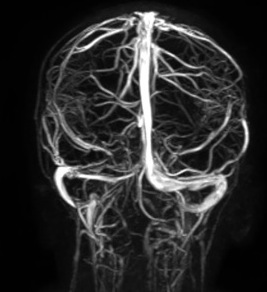

La risonanza dell’encefalo e l’angio-RM di controllo mostravano un quadro di ricanalizzazione a livello del seno sigmoideo, ma con un assottigliamento del segnale di flusso nell’emiporzione destra del seno trasverso, in prossimità della confluenza con il seno sagittale (Figura 3). Abbiamo deciso, vista la parziale ricanalizzazione, di continuare la terapia anticoagulante, al termine della quale la bambina eseguirà lo screening trombofilico.